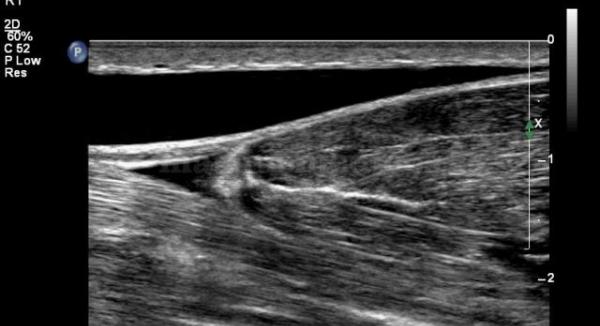

Los días 26 y 27 de mayo la Facultad de Ciencias de la Salud impartirá un curso básico de ecografía musculoesquelética dirigido a fisioterapeutas, con la colaboración de Sanro electromedicina.